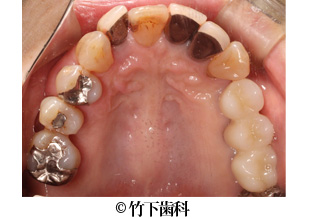

【症例2】右下臼歯部3本欠損のインプラントによる治療

- 治療前

- 治療後

- 治療名

- 右下臼歯部3本欠損のインプラントによる治療

- 費用

- 605,000円(税込)

【内訳】

インプラント埋入術

220,000円(税込) × 2

インプラント上部構造

55,000円(税込) × 3

- 期間

- 5ヵ月

- 通院回数

- 11回

- 患者様

- 50代女性

治療内容

患者様の症状

部分入れ歯を長年使用していて、奥歯で噛むことに困難を感じていました。食べ応えのあるものをしっかりと噛みたいというご希望がありました。

治療法

下顎の欠損部分に2本の人工の歯根を埋入しました。そこに3本の歯の形をしたブリッジの上部構造を装着しました。

治療結果

インプラント埋入術によって人工歯根を形成し、その上に上部構造を作ったことで、ご本人の歯のように安定して食べものを噛めるようになりました。2本のインプラントにブリッジの上部構造を装着することで、3本の歯があるような見た目になりました。

そのほか

患者様のご希望を聞いて、天然歯はなるべく残すような治療をしています。

※治療結果は患者様によって個人差があります。

治療を行う上での 注意点 (リスク・副作用)

出血、腫脹、疼痛、神経麻痺、補綴物のダツリ、破折、インプラント体の破折、咬合違和感、インプラント周囲炎